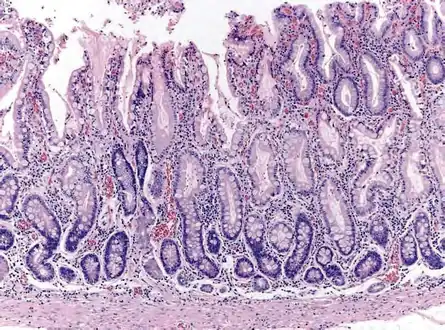

Atrophic gastritis

Atrophic gastritis under low power. H&E stain.

Histopathology of antral mucosa with atrophy. H&E 10x. Antral gastric mucosa with accentuated atrophy because replacement by extensive intestinal metaplasia.